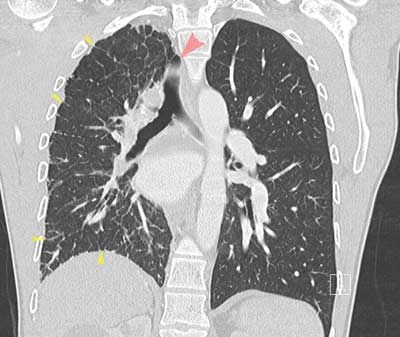

Figure 1

CECT of the thorax, lung window, coronal reformatted image. Hyperinflation of the left lung, smaller volume of the right lung. Mediastinal shift to the right side (red arrow pointing to displaced trachea). Thickened intralobular and interlobular septa (yellow arrows).